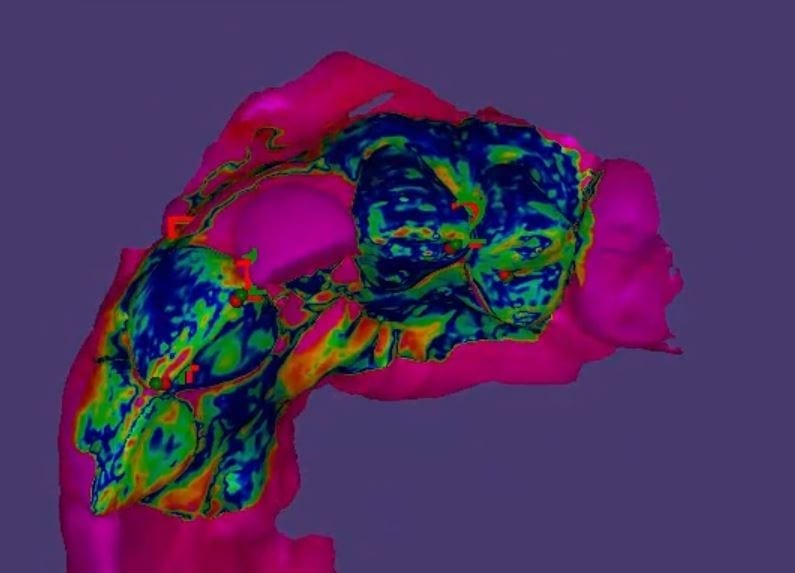

Once you import in the pre-op condition, you can manually relate the models to each other by identifying common landmarks between the two models. After you perform alignment, you can then click on “Best fit matching”. The color scheme in exocad is a great guide in letting you know how well you have articulated the models together.

The more blue you see in the Korolated models, the more reliable your stitch is and you can be assured of greater accuracy in your final restoration.